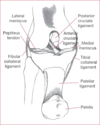

Pincer lesion

acetabulum extends out too far and “pincers” the femoral head causing FAI

CAM lesion

“knuckle” of bone coming out of the femoral neck seen in FAI

Internal snapping hip

groin pain caused by iliopsoas tending snapping over the iliopectineal eminence, commonly seen in dancers

External snapping hip

pain in lateral thigh due to a tight IT band or gluteus maximus snapping over the greater trochanter

Commonly mistaken for greater trochanteric bursitis